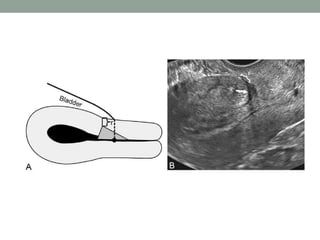

The document discusses the concept of cesarean scar niche, defining it as indentations in the myometrium that can lead to various complications such as uterine rupture and adverse reproductive effects. Factors contributing to this condition include surgical techniques and patient-related issues, with symptoms like pelvic pain and spotting. Diagnostic methods and potential treatment options, including medical therapy and surgical correction, are also highlighted.